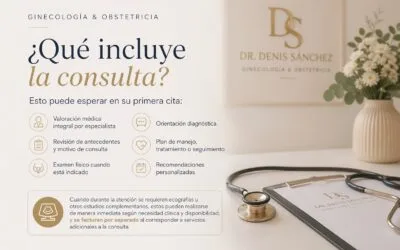

¿Qué incluye la consulta ginecológica u obstétrica? Qué esperar en su primera cita con el Dr. Denis Sánchez

Una de las preguntas más frecuentes antes de agendar es: “¿Qué incluye la consulta?”. Y es una...